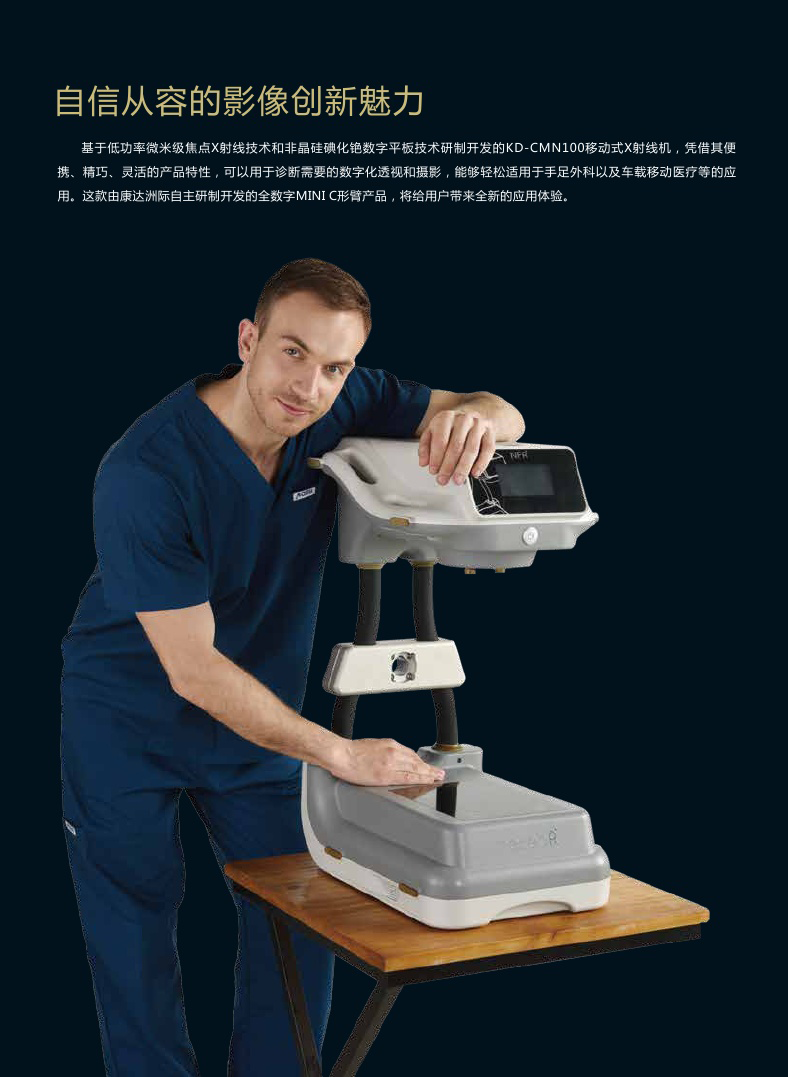

KD-CMN100

移动式数字MINI C形臂

KD-CMN100 是一款灵巧便捷的新型数字 X 射线影像系统,由康达洲际自主研制开发,用于诊断需要的数字化透视和摄影,适用于临床医疗/运动损伤/科研等领域。

紧凑灵活的台式C臂结构设计

便捷、精巧、灵活是 CMN100 带给用户最直观的体验和感受。 从整机的结构设计以及占地和重量考虑,均立足于手足外科的临床应用需要。

紧凑的设计强化设备的流动性、通用性和灵活性

紧凑的 MINI C 臂设计,比普通 C 形臂移动性能更好,方便患者的检查并提高被检对象的流动性;

简易的操作流程和 83KG 的整机重量,普通大夫或护士单人即可驱动操控;

不足 1 平米的空间占地,可以自由穿梭在手术室间甚至病床旁。

更符合手足外科临床开展的 “ 台式 ”C臂结构设计

与常见的“轴式”C 臂结构设计不同的是,CMN100 采用全新的”台式”C 臂结构与”轴式“显示控制相结合的操作控制。

根据手足外科的临床应用特点,医生是通过改变患者的肢体角度来改变投照角度、而无需调整 C 臂角度,

即通常医生将探测器平面作为一个“操作台”,不需要像其它 C 臂那样改变 C 臂角度,显然这样的台式结构更利于手术操作和图像观察,使得设备设计能够充分与手术场景融合。